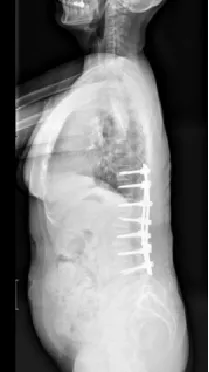

▲ 男,14岁,早发性脊柱侧弯、先天性脊柱畸形